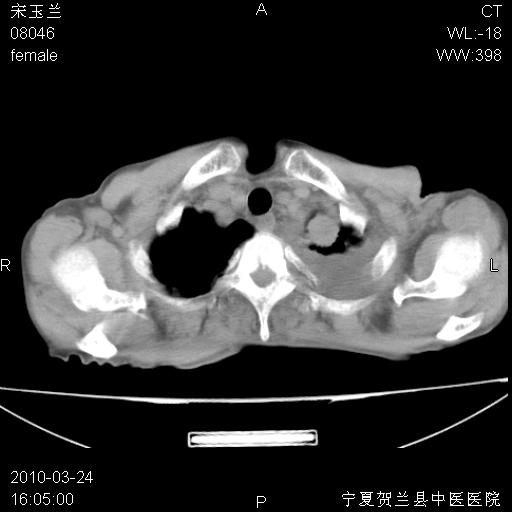

以下是引用zxl51642在2010-3-24 18:49:00的发言:[br]结合乳腺癌术后病史,考虑双肺及纵隔淋巴结多发转移、左侧胸膜转移并左侧大量胸水、左下肺膨胀不全。